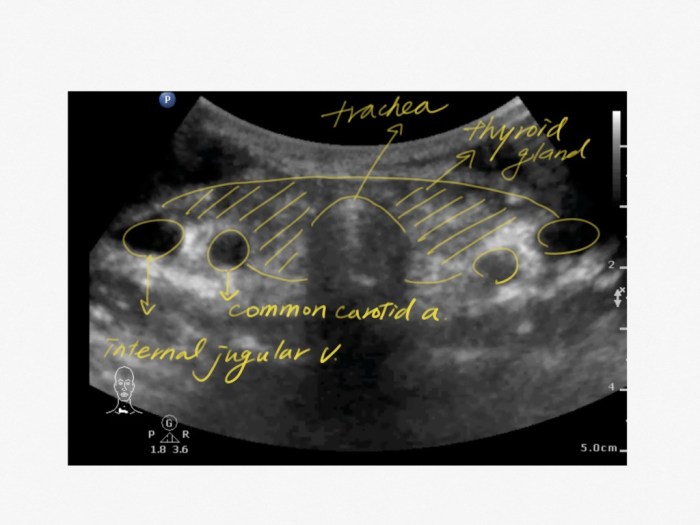

在許哲彰醫師寫的Trachea Sonoanatomy文章中有提到

Moth sign,

雙翼的兩個圓形結構就是今天的標的: Internal jugular vein

呼吸道掃描時,主角是氣管,所以探頭放中間,

CVC掃描時,主角是IJV,所以要將探頭往外側移動,讓IJV在螢幕的中心。